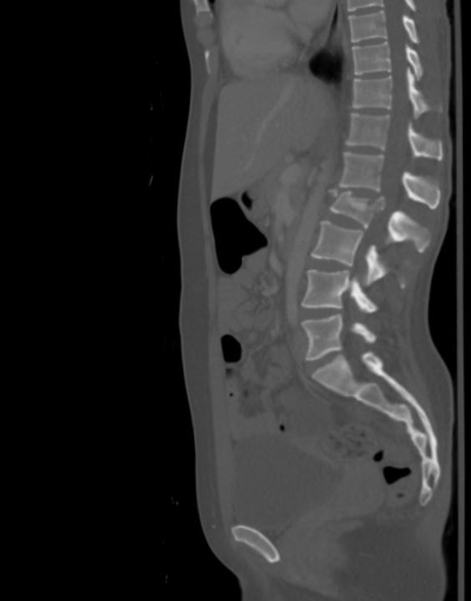

What’s the Diagnosis? Gepost op 11 oktober 201911 oktober 2019 door netwerkvsseh What’s the Diagnosis? @emdaily.cooperhealth.org Dit delen: Delen op X (Opent in een nieuw venster) X Share op Facebook (Opent in een nieuw venster) Facebook Delen op LinkedIn (Opent in een nieuw venster) LinkedIn E-mail een link naar een vriend (Opent in een nieuw venster) E-mail Afdrukken (Opent in een nieuw venster) Print Vind-ik-leuk Aan het laden... Gerelateerd